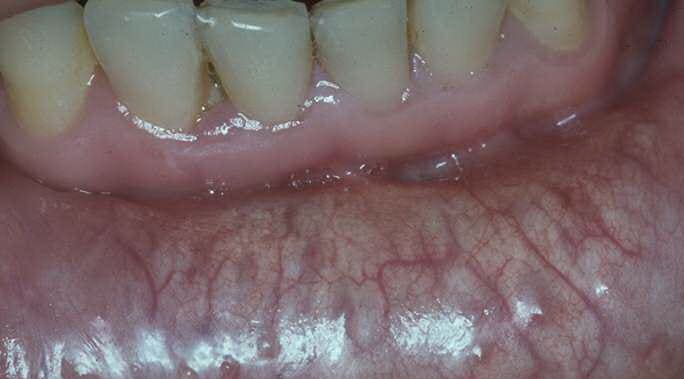

The cutaneous lesions usually appear first in the second or third decade of life and are generally progressive in extent and severity. They consist of soft, yellowish, coalescing papules, and the affected skin appears loose and wrinkled. The sides of the neck, the axillae, and the groin are the most common sites of lesions . In the eyes, so-called angioid streaks of the fundi may cause progressive impairment of vision. Involvement of the arteries of the gastric mucosa may lead to gastric hemorrhage; involvement of coronary arteries may result in attacks of angina pectoris, although myocardial infarction is rare; and involvement of the large peripheral arteries may cause intermittent claudication . Radiologic examination in such cases reveals extensive calcification of the affected peripheral arteries . |